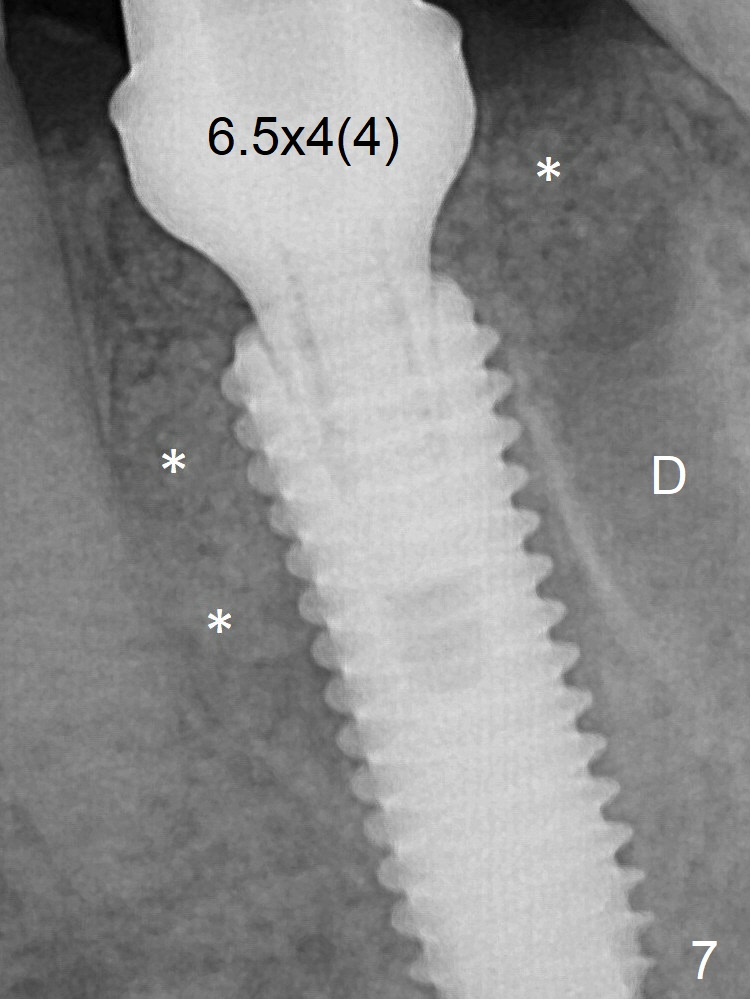

Due to severe buccal plate resorption, a shorter implant is placed (Fig.6; 5x15 mm in stead of 18 mm). There is at least 2 mm gap buccally for Vanilla Graft, which is also placed next to the implant and the neighboring root (Fig.7 double * ). Abutment: 6.5x4(4) mm. The distal (D) socket is packed with Collagen Plug before bone graft coronally (single *). Both the mesial and distal sockets heal 5.5 months postop (Fig.9), although the apical portion of the distal socket was not filled with allograft (Fig.7 D). The implant was placed mesial. The abutment may be changed to 5.5x5(3) mm or 4.5x15 degrees 3 mm cuff before impression. Next case, osteotomy should be established in the middle of the socket by using Lindamann bur amply.

Bone Shorter Than Expected Last Next Xin Wei, DDS, PhD, MS 1st edition 12/07/2017, last revision 09/02/2018